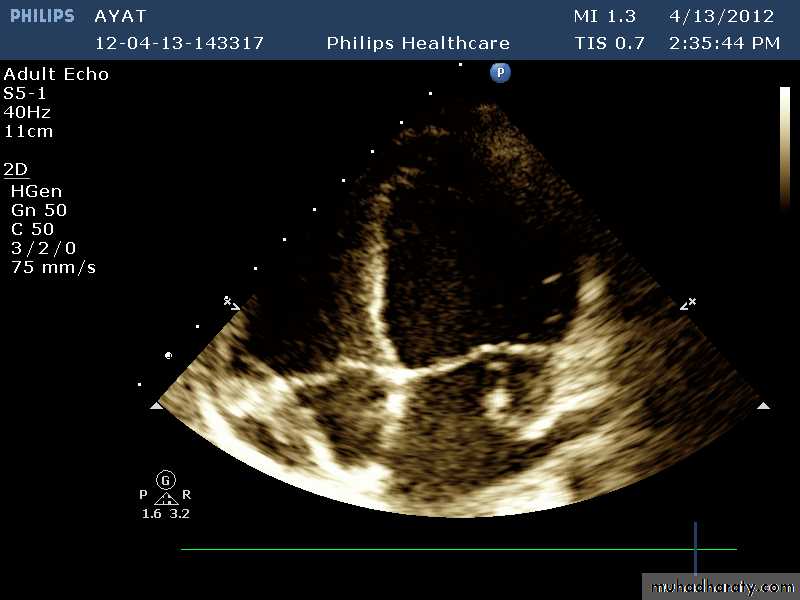

VEGETATIONS

36

37

38

39

40